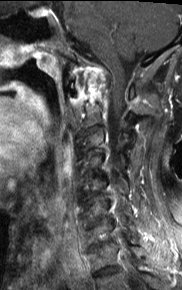

#CaseOfTheWeek‼️🥳‼️ ☢️🩻☠️Case#22☠️🩻☢️ #Mass 📲➡️➡️#Diagnosis❔❓❔ #FOAMRad #RadEd #MedEd #OrthoEd #OrthoTwitter @ssr_rwg @UWRadRes @ISSVA_org